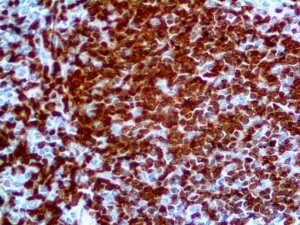

It is the ICU physician who is most likely to witness one of the deadliest manifestations of the abnormal immunological response, the cytokine storm syndrome (CSS). This response is also referred to by some as the cytokine release syndrome (CRS). CSS is characterized by continuous activation and expansion of macrophage and lymphocyte populations, which secrete large amounts of cytokines, causing the cytokine storm. This massive cytokine release is akin to hemophagocytic lymphohistiocytosis (HLH) disease, a syndrome characterized by initial unchecked and persistent activation of cytotoxic T lymphocytes and NK cells.

Clinical and laboratory manifestations of HLH include fever, enlarged liver and/or spleen, neurologic dysfunction, coagulopathy, liver dysfunction, cytopenias (i.e., low levels of erythrocytes, leukocytes, and/or platelets), hypertriglyceridemia, hyperferritinemia, hemophagocytosis, and eventually diminished NK cell activity as the immune system becomes progressively paralyzed. HLH can be familial (primary HLH) or secondary to another disease process (sHLH), such as rheumatic disease, in which it is referred to as macrophage activation syndrome (MAS, characterized by elevated ferritin).